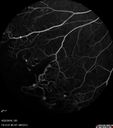

Coats' Disease - 14 year old - Asymptomatic501 viewsPresented with macular exudates. Temporal macroaneurysms responded to laser. Ultra-wide field FA shows nonperfusionNov 07, 2016

Coats' Disease - 14 year old - Asymptomatic477 viewsPresented with macular exudates. Temporal macroaneurysms responded to laser. Ultra-wide field FA shows nonperfusionNov 07, 2016

Coats' Disease - 14 year old - Asymptomatic478 viewsPresented with macular exudates. Temporal macroaneurysms responded to laser. Ultra-wide field FA shows nonperfusionNov 07, 2016

Coats' Disease - 14 year old - Asymptomatic482 viewsPresented with macular exudates. Temporal macroaneurysms responded to laser. Ultra-wide field FA shows nonperfusionNov 07, 2016

Coats' Disease - 14 year old - Asymptomatic527 viewsPresented with macular exudates. Temporal macroaneurysms responded to laser. Ultra-wide field FA shows nonperfusionNov 07, 2016

Coats' Disease - 14 year old - Asymptomatic507 viewsPresented with macular exudates. Temporal macroaneurysms responded to laser. Ultra-wide field FA shows nonperfusionNov 07, 2016

Coats' Disease - 14 year old - Asymptomatic481 viewsPresented with macular exudates. Temporal macroaneurysms responded to laser. Ultra-wide field FA shows nonperfusionNov 07, 2016

Coats' Disease - 14 year old - Asymptomatic655 viewsPresented with macular exudates. Temporal macroaneurysms responded to laser. Ultra-wide field FA shows nonperfusionNov 07, 2016